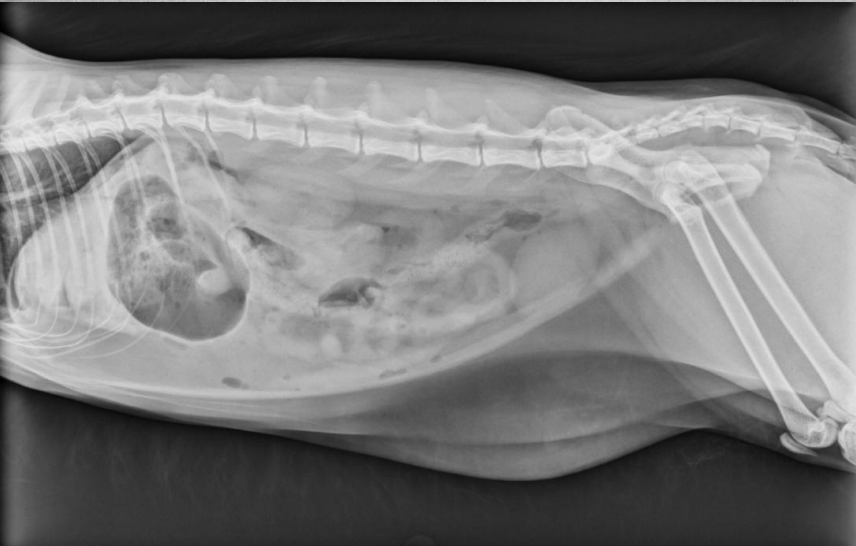

15 yo cat

Weight loss, anorexia, vomiting

Findings:

● Dilated bowel filled with fecal mass

– Not only large intestine, but small

intestine as well.

● Megacolon